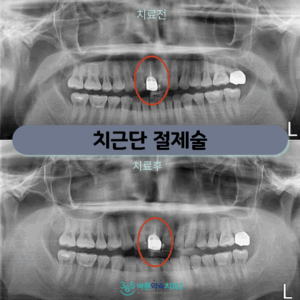

망원동치과 자연치아를 살리는 치료

망원동치과 자연치아를 살리는 치료 심한 충치나 외상 등 다양한 원인으로 인해 치아 뿌리에 손상이나 염증이 생기게 된다면 신경치료를 통해 증상을 가라앉히는 치료를 진행하지만 신경치료를 받았음에도 불구하고 통증이 지속되고 치아 뿌리…